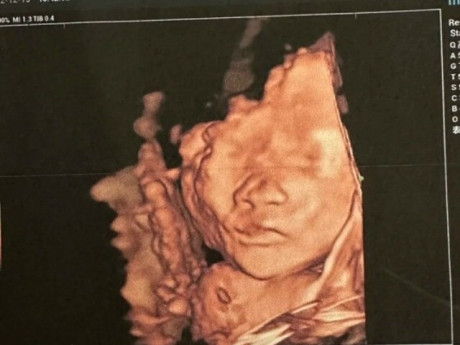

Bà bầu - Hết Tết ôm bụng bầu lên phố mưu sinh, chồng bất ngờ đòi ở lại còn chìa ra giấy siêu âm của một người khác

Bà bầu - Nhập viện vì trúng gió, cổ tử cung cô gái bất ngờ mở to rồi đẻ con, không hề biết đang mang bầu

Bà bầu - Tờ giấy khám thai lạ trong ngăn tủ khiến tôi có cái nhìn khác về người chồng "hướng nội", thủy chung của mình